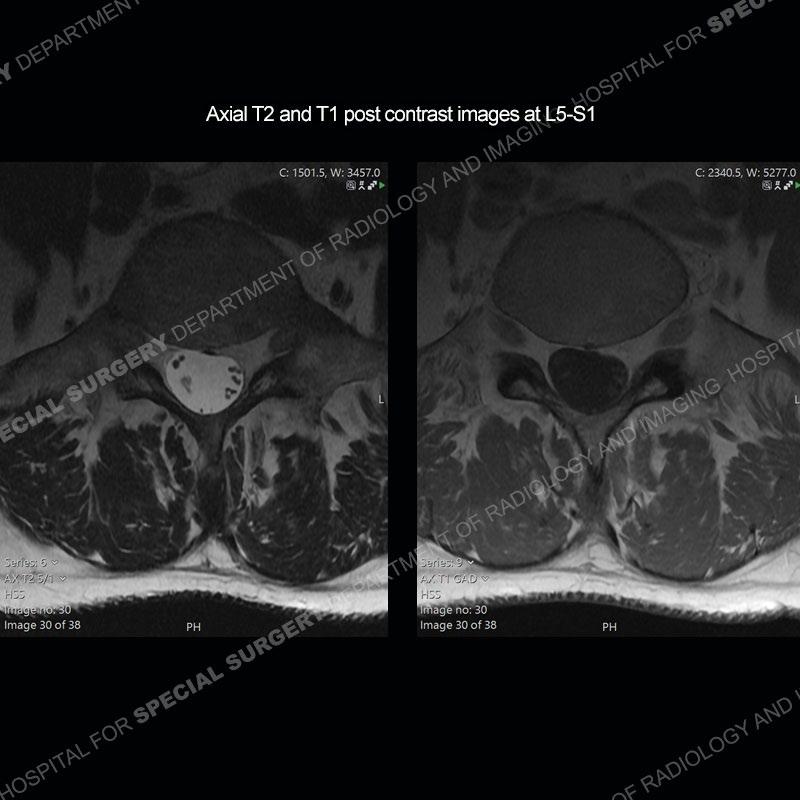

Post operative changes are seen on the left side at L5-S1 where there is near complete removal of the left sided L5 lamina, partial resection of the left L5-S1 facet joint, and resection of the left sided ligamentum flavum. In the anterolateral epidural space about the subarticular recess is a mass that demonstrates similar T1 and T2 signal characteristics to the adjacent degenerated disc. There is enhancement about the periphery of the mass, but the majority of this somewhat geographic or polyploid mass demonstrates no enhancement. The mass exerts prominent mass effect on the left S1 axillary sleeve/proximal nerve root. The left S1 nerve root shows enlargement and increased enhancement as compared to the contralateral right side.

Diagnosis: Recurrent Disc Herniation

Not as much of a diagnostic dilemma as some other cases but more so just a very nice example of what can be a difficult assessment at times. The evaluation of granulation tissue/scar/epidural fibrosis vs. disc herniation particularly in the earlier post operative period can be very difficult. Clues that can assist in identifying a disc herniation are a more geographic or polypoid nature to the mass, signal characteristics similar to the adjacent degenerated disc, mass effect upon the thecal sac/adjacent neural structures, and a typical enhancement pattern. As the disc material is avascular, as long as imaging is performed in a relatively rapid fashion after contrast administration (within 20-30 minutes), the granulation tissue around the disc will enhance but the disc material itself will not. If there is a marked delay between contrast administration and imaging, there may be diffusion of contrast into the disc making the assessment very difficult. The marked utility of contrast to help delineate disc vs. scar has led to our institution employing contrast fairly uniformly within the first two years following surgery.